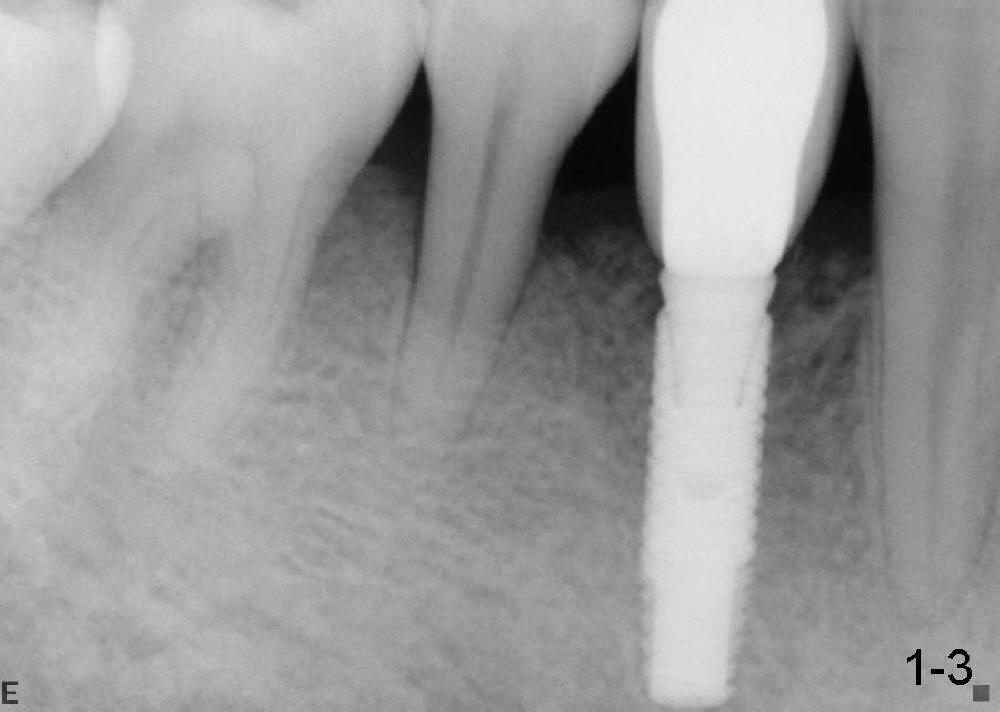

沐旭升医师送来两例植骨病例:第一例使用金属网(图一);第二例上颌骨头高度3.4 mm (CT 显示),上颌窦提高术植骨(侧面进路),同期植牙(图二)。打开每张图看评论。

Case1 is bone graft with metal mesh. Case 2 is bone graft with sinus lift through window, since the  existing bone only has 3.4 mm in the CT film (英文部分由沐医生提供).